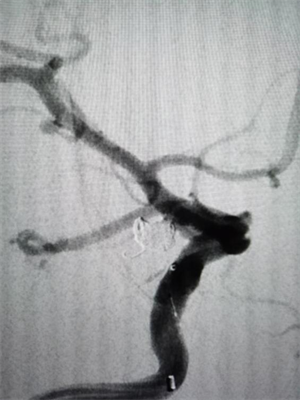

椎动脉狭窄的“通路攻坚战”

同样在元宵节当天,75岁的黄奶奶因头晕、意识丧失被送医。检查发现其左侧椎动脉闭塞、右侧椎动脉重度狭窄,广泛动脉硬化斑块形成。神经内科介入团队评估后,为其实施了脑血管造影+经皮椎动脉支架置入术。手术顺利完成,黄奶奶术后头晕症状消失。这一案例再次提醒中老年人群,尤其是有血管病危险因素的人,定期进行血管检查十分必要。

△图一:手术前右侧椎动脉重度狭窄

△图二:手术椎动脉置入支架后